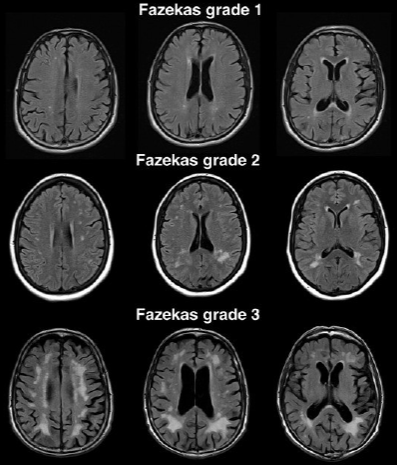

Шкала Fazekas

Шкалу Fazekas используют для простой оценки тяжести поражения белого вещества головного мозга по количеству и размеру гипертенсивных очагов лейкоареоза в белом веществе на Т2-взвешенных изображениях. Обычно такие очаги связывают с болезнью мелких сосудов головного мозга, хотя очевидно, что не все такие очаги обусловлены именно этим.

Шкала включает три степени:

Fazekas 1 — минимальные изменения, мелкие точечные гиперинтенсивные очаги в белом веществе, которые могут быть связаны с начальной стадией микроангиопатии или возрастными изменениями.

Fazekas 2 — умеренные изменения, отдельные гиперинтенсивные очаги и их слияния. Эти изменения могут указывать на наличие более выраженных сосудистых заболеваний мозга.

Fazekas 3 — значительные изменения с крупными сливными зонами, что обычно свидетельствует о наличии серьёзных сосудистых заболеваний и высоком риске развития деменции.